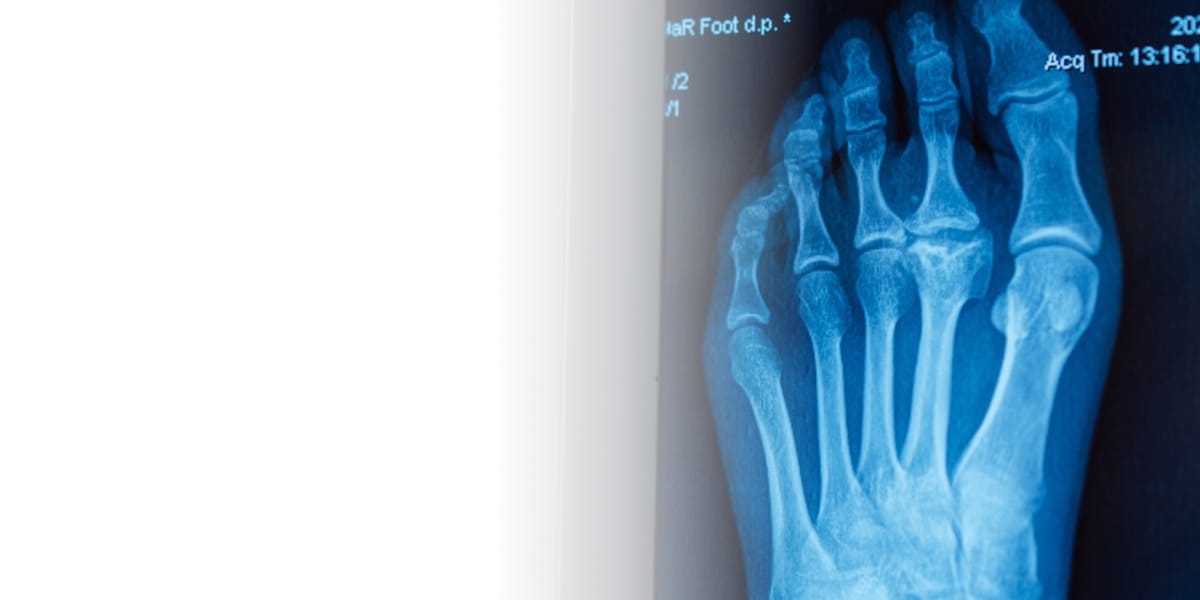

Компьютерная томография (КТ) стопы — это один из самых информативных современных диагностических методов. По результатам проведения КТ доктор получает возможность выполнить точную диагностику патологий костных структур. В некоторых случаях по специальным показаниям и назначению лечащего врача процедура проводится с внутривенным контрастированием (КТ с контрастом), что дополнительно дает возможность оценить состояние сосудов и мягких тканей, выявить новообразования, оценить нарушения кровотока в крупных сосудах.

КТ стопы позволяет провести оценку состояния костных структур, а в случае использования контраста — сосудов крупного и среднего калибра, наличие новообразований мягких тканей. КТ дает возможность диагностировать большинство заболеваний, вызывающих воспаление или деформацию костей и суставов, в частности, артроз, артрит, остеомиелит. Также КТ показывает деформации, аномалии развития стопы. КТ с высокой степенью детализации показывает состояние костей после переломов.

Врач назначает КТ стопы в тех случаях, когда необходимо получить точные данные о состоянии внутренних структур.

● травмы различной сложности

● деформации или аномальное развитие стопы (вальгусная деформация, плоскостопие)

● воспалительные и дегенеративные процессы (артроз, артрит, остеомиелит)

● боли неясной этиологии

● подготовка к хирургическому вмешательству или контроль после операции.

● подозрение на облитерирующий атеросклероз артерий

● подозрение на наличие объемных образований